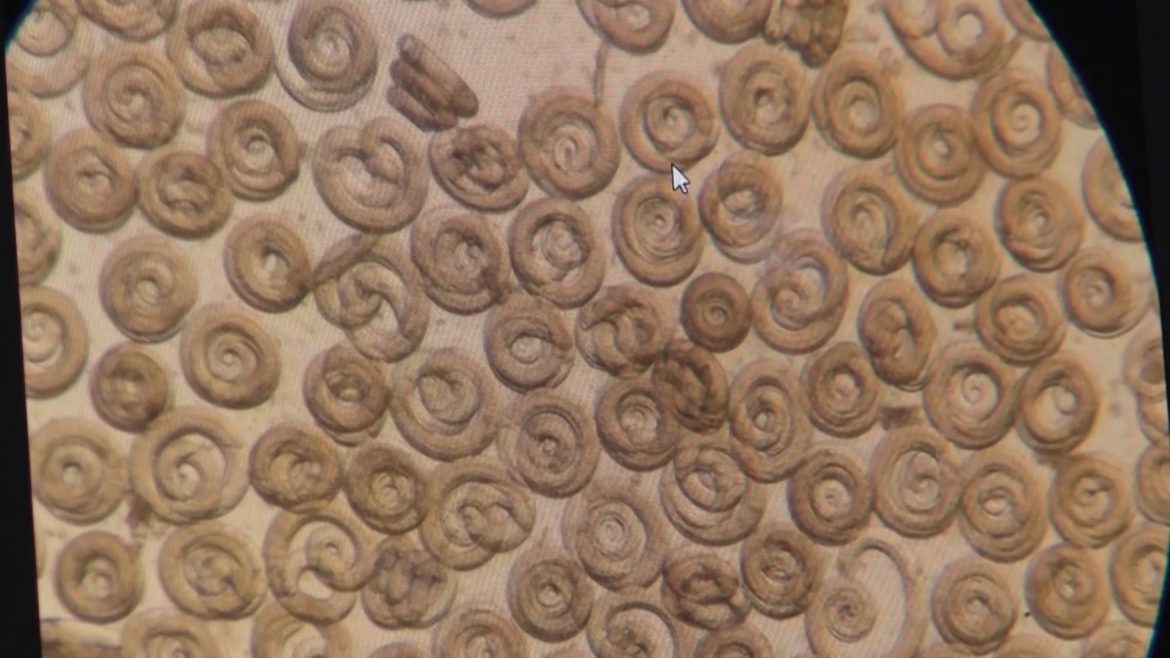

„Trichinella spiralis се у облику ларве налази у попречно пругастим мишићима. Када се мишићна влакна, под дејством желудачних сокова, разграде, у организму новог домаћина ослобађају се ларве које улазе у слузокожу танког црева. За неколико дана достижу полну зрелост. После оплодње мужјаци угину, а женке почињу да полажу ларве. Младе ларве напуштају слузокожу, путем лимфе доспевају у крвоток, а затим у мишиће, где се учауре. Ларве у мишићима могу преживети годинама, чекајући новог домаћина. Тако се формирају жаришта трихинелозе. Човек може постати жртва ако користи заражено месо у исхрани. У том случају се читав биолошки циклус паразита одвија и у људском организму*,“ објашњава др Дмитрић.

Одрaсли паразит живи у цревима домаћина око месец дана и за то време избаца огроман број ларви. У мишићима се оне учауре и могу преживети и до три деценије. Појава болести код људи зависи и од кулинарских навика. Болест се јавља након конзумирања зараженог меса, кобасица и сушених прерађевина које нису довољно термички обрађене.